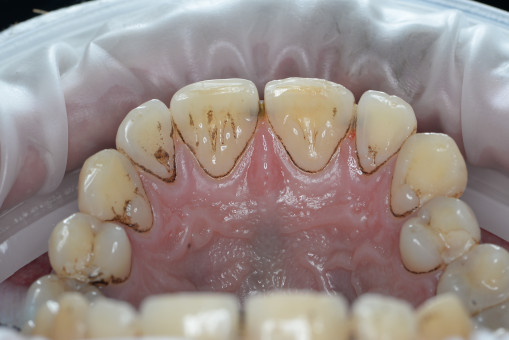

А прежде, чем вы посмотрите фотографии «до» и «после» лечения слизистой оболочки полости рта, проведенных в нашей клинике, хочу поблагодарить большое количество наших пациентов, которые поверили, прониклись нашей концепцией, и мы вместе, именно вместе победили болезни десны, гингивит и пародонтит!

До/после лечения